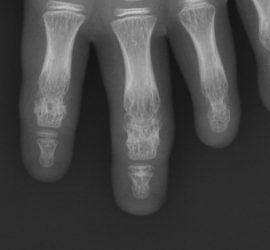

HIPOFALANGIAS E ADACTILIAS DEDOS CURTOS E AUSENTES

HIPOFALANGIAS E ADACTILIAS DEDOS CURTOS E AUSENTES Como se manifestam as deformidades? Vamos falar de um largo número de deformidades que se podem manifestar de uma forma muito variável: – Manifestações ligeiras, pouco percetíveis ou moderadamente percetíveis com encurtamento duma falange num ou em dois dedos (Fig. 1 e 2). […]